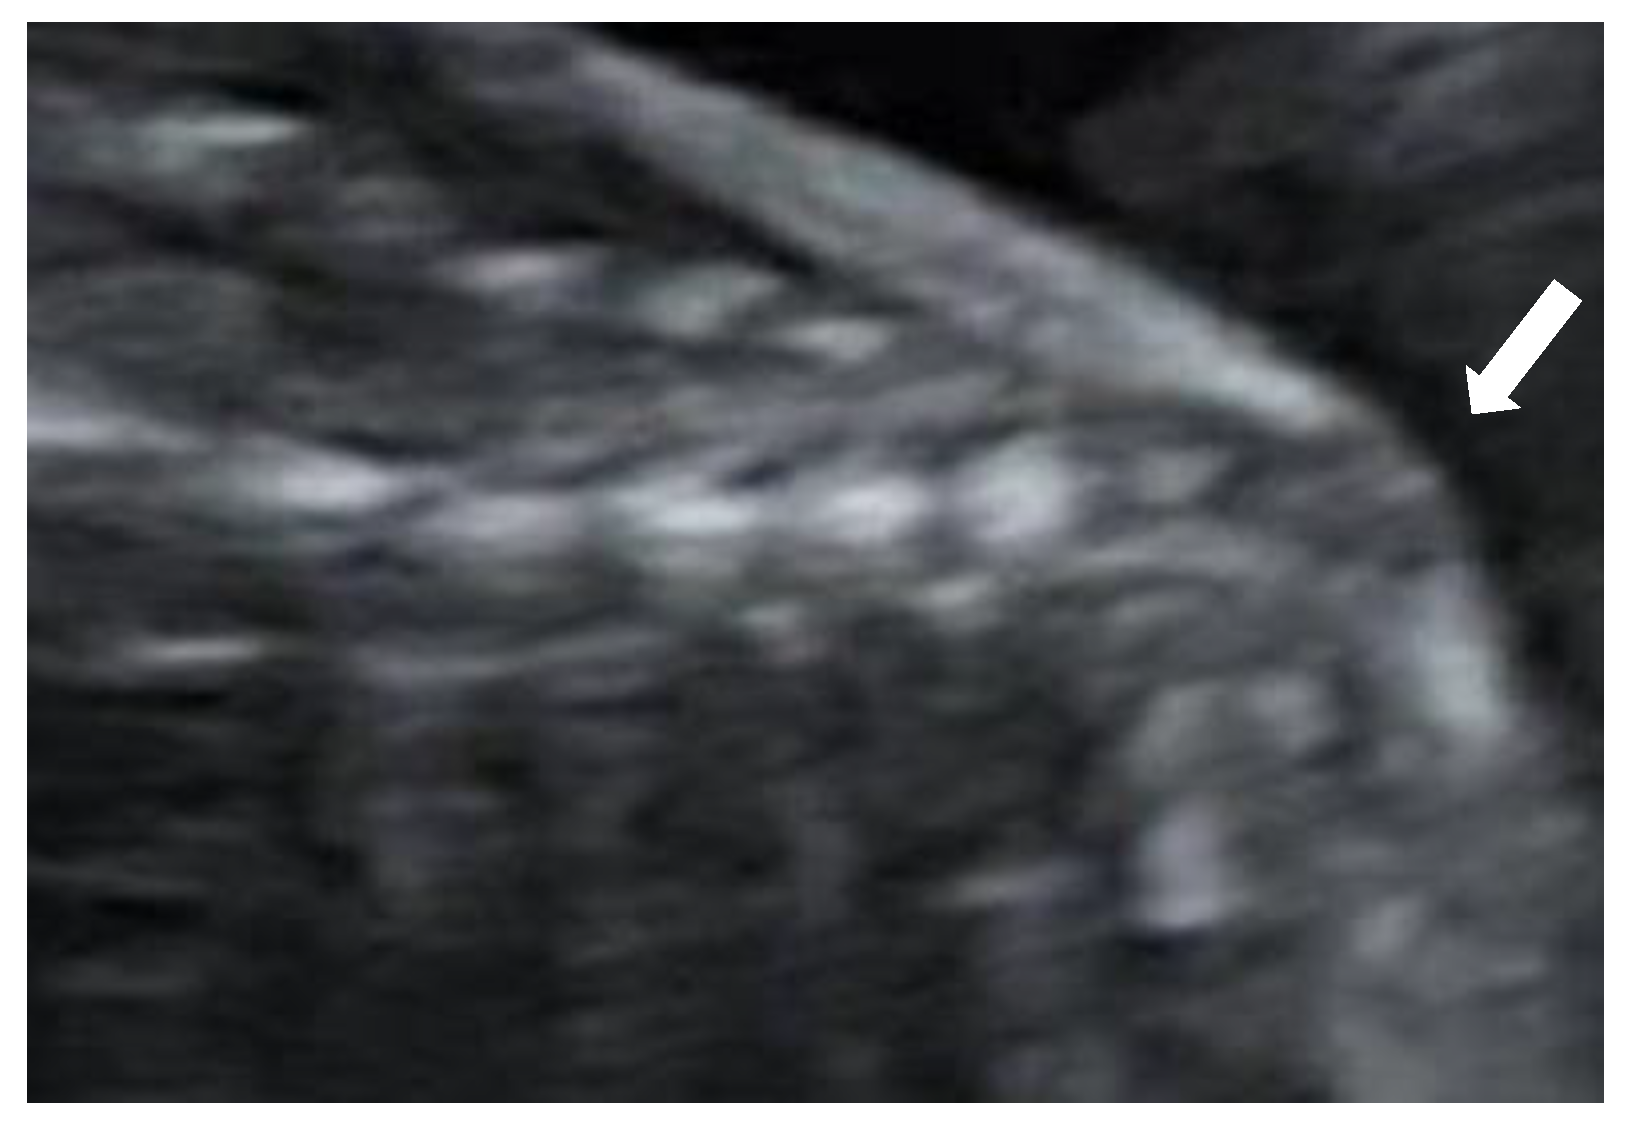

Figure 2). The lateral ventricles were not dilated. Ultrasound examination of the spine revealed a closed skin except for a minimal fistula in the sacro-coccygeal region (

Figure 3,

Figure 4 and

Figure 5). Furthermore, an abnormal gap between the second and third digit was seen on both hands as well as a syndactyly between the first and second toe. Cardiac sonography was normal at both 17- and 24-weeks GA, with a normal four-chamber view, outflow tracts, and three-vessel view. An amniocentesis was performed to rule out genetic anomalies and to measure alfa 1-fetoprotein. Additionally, a fetal MRI was carried out mainly to assess the fetal spine, as the cerebral findings all indicated the presence of an open neural tube defect. MRI analysis confirmed the hydroureteronephrosis as well as the lemon-shaped skull, Arnold–Chiari malformation 11mm below the foramen magnum, absent cerebrospinal fluid around the cerebellum, and possible mild tethering of the cord. However, MRI failed to demonstrate an open spina bifida or any skin defects. The Alfa 1-fetoprotein was elevated, further reinforcing the assumption of a classic spina bifida. QF-PCR showed no aneuploidy for chromosomes 13, 18, 21, X, or Y, but SNP array demonstrated a terminal multiplication of approximately 56 Mb of the long arm (3q23qter) of chromosome 3: arr 3q23q29(141903905-197845233)x2~4. The nature of the multiplication could not be deduced. Interphase FISH with probes in chromosomal regions 3q26 and 3q27 showed 4 copies of both chromosomal bands in approximately 50% of the interphases. Metaphase FISH proved that the 2 extra copies were located on a marker chromosome. Chromosomal examination of the parents showed no anomalies, demonstrating that the aberration occurred de novo in the fetus. Note, a genome-wide NIPT analysis on a blood sample taken at 27 weeks GA failed to detect this anomaly despite its size, indicating this to be a true fetal mosaicism of type 5 (TFM5).

9]. The diagnoses can be made in subtle cases, such as this one, by identifying a lower position of the conus medullaris. On the other hand, it is a difficult examination that is not suitable for routine screening but can help if suspicion is raised. Dorsal dermal sinuses are even more difficult to diagnose, as there is no presence of a cyst or mass. In these cases, the nerves and spinal cord are not usually affected and, therefore, in contrast to open lesions, this disease has a minimal functional impact. To our knowledge, this is the first case of closed spina bifida with a dorsal dermal sinus that is accompanied by secondary cranial abnormalities that has been diagnosed prenatally. In this fetus, a severe hindbrain herniation was detected while prenatal imaging demonstrated an intact spine and skin, both on MRI and ultrasound. Only by means of expert ultrasound, after increased suspicion of the diagnosis of spina bifida due to the elevated alfa 1-fetoprotein, could we find a small fistula between the skin and the spinal canal.